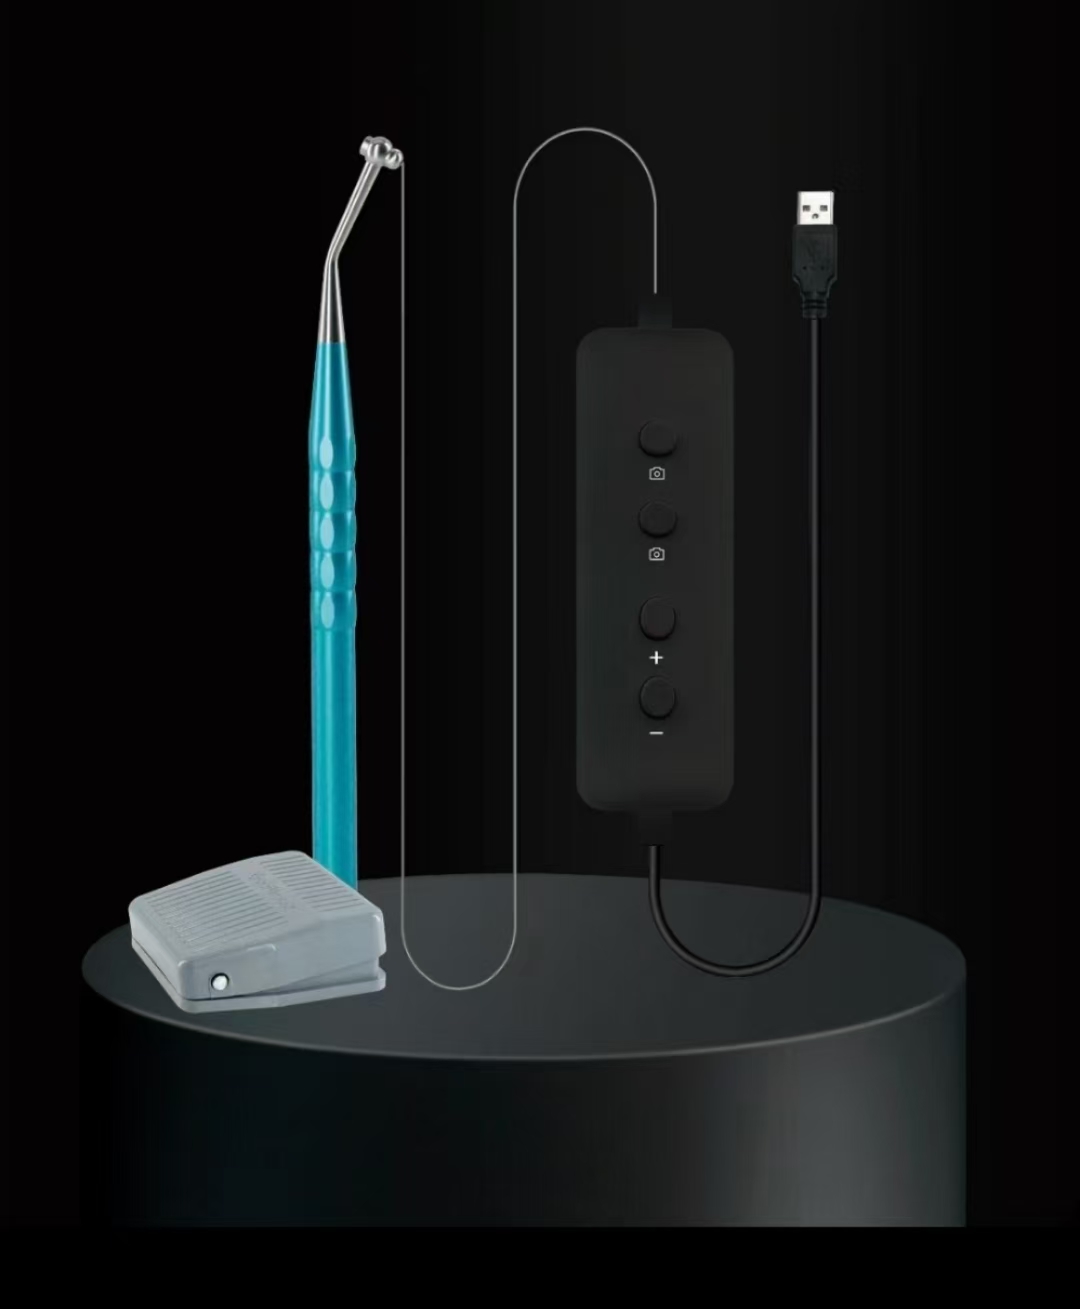

* With WIFI Padel to take image, higher efficient to work, more convenient

* Comes with system

* Full Light color temperature: 6000K-6500K white light

* Image viewing angle: diagonal 88°

* USB output